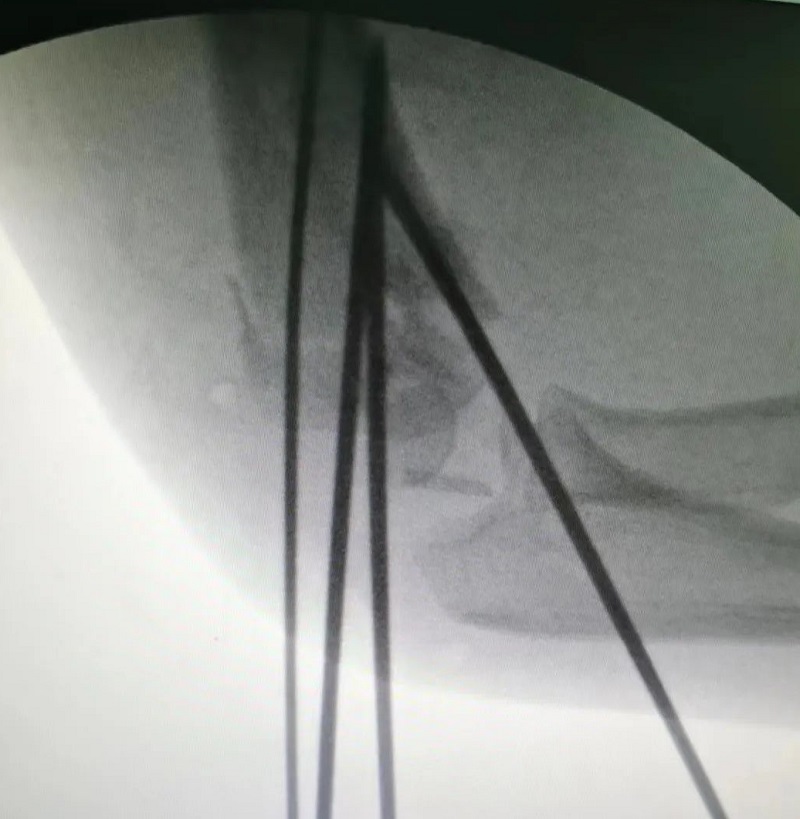

(术中透视)